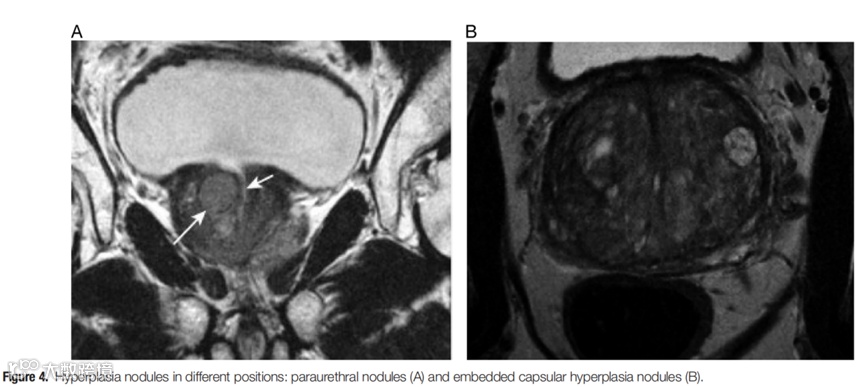

Emphasis on the management of embedded capsular hyperplasia nodules associated with benign prostatic hyperplasia

重视前列腺外科包膜镶嵌增生结节的处理

本文通过对良性前列腺增生(BPH)患者手术治疗中包膜镶嵌增生结节的精细化管理,强调了前列腺包膜层面和增生结节残留对术后并发症及二次手术的深远影响。特别是铥激光前列腺剜除术在处理包膜镶嵌结节方面的优势,展示了其在前列腺外科手术中的重要地位,具有较高的临床应用价值。